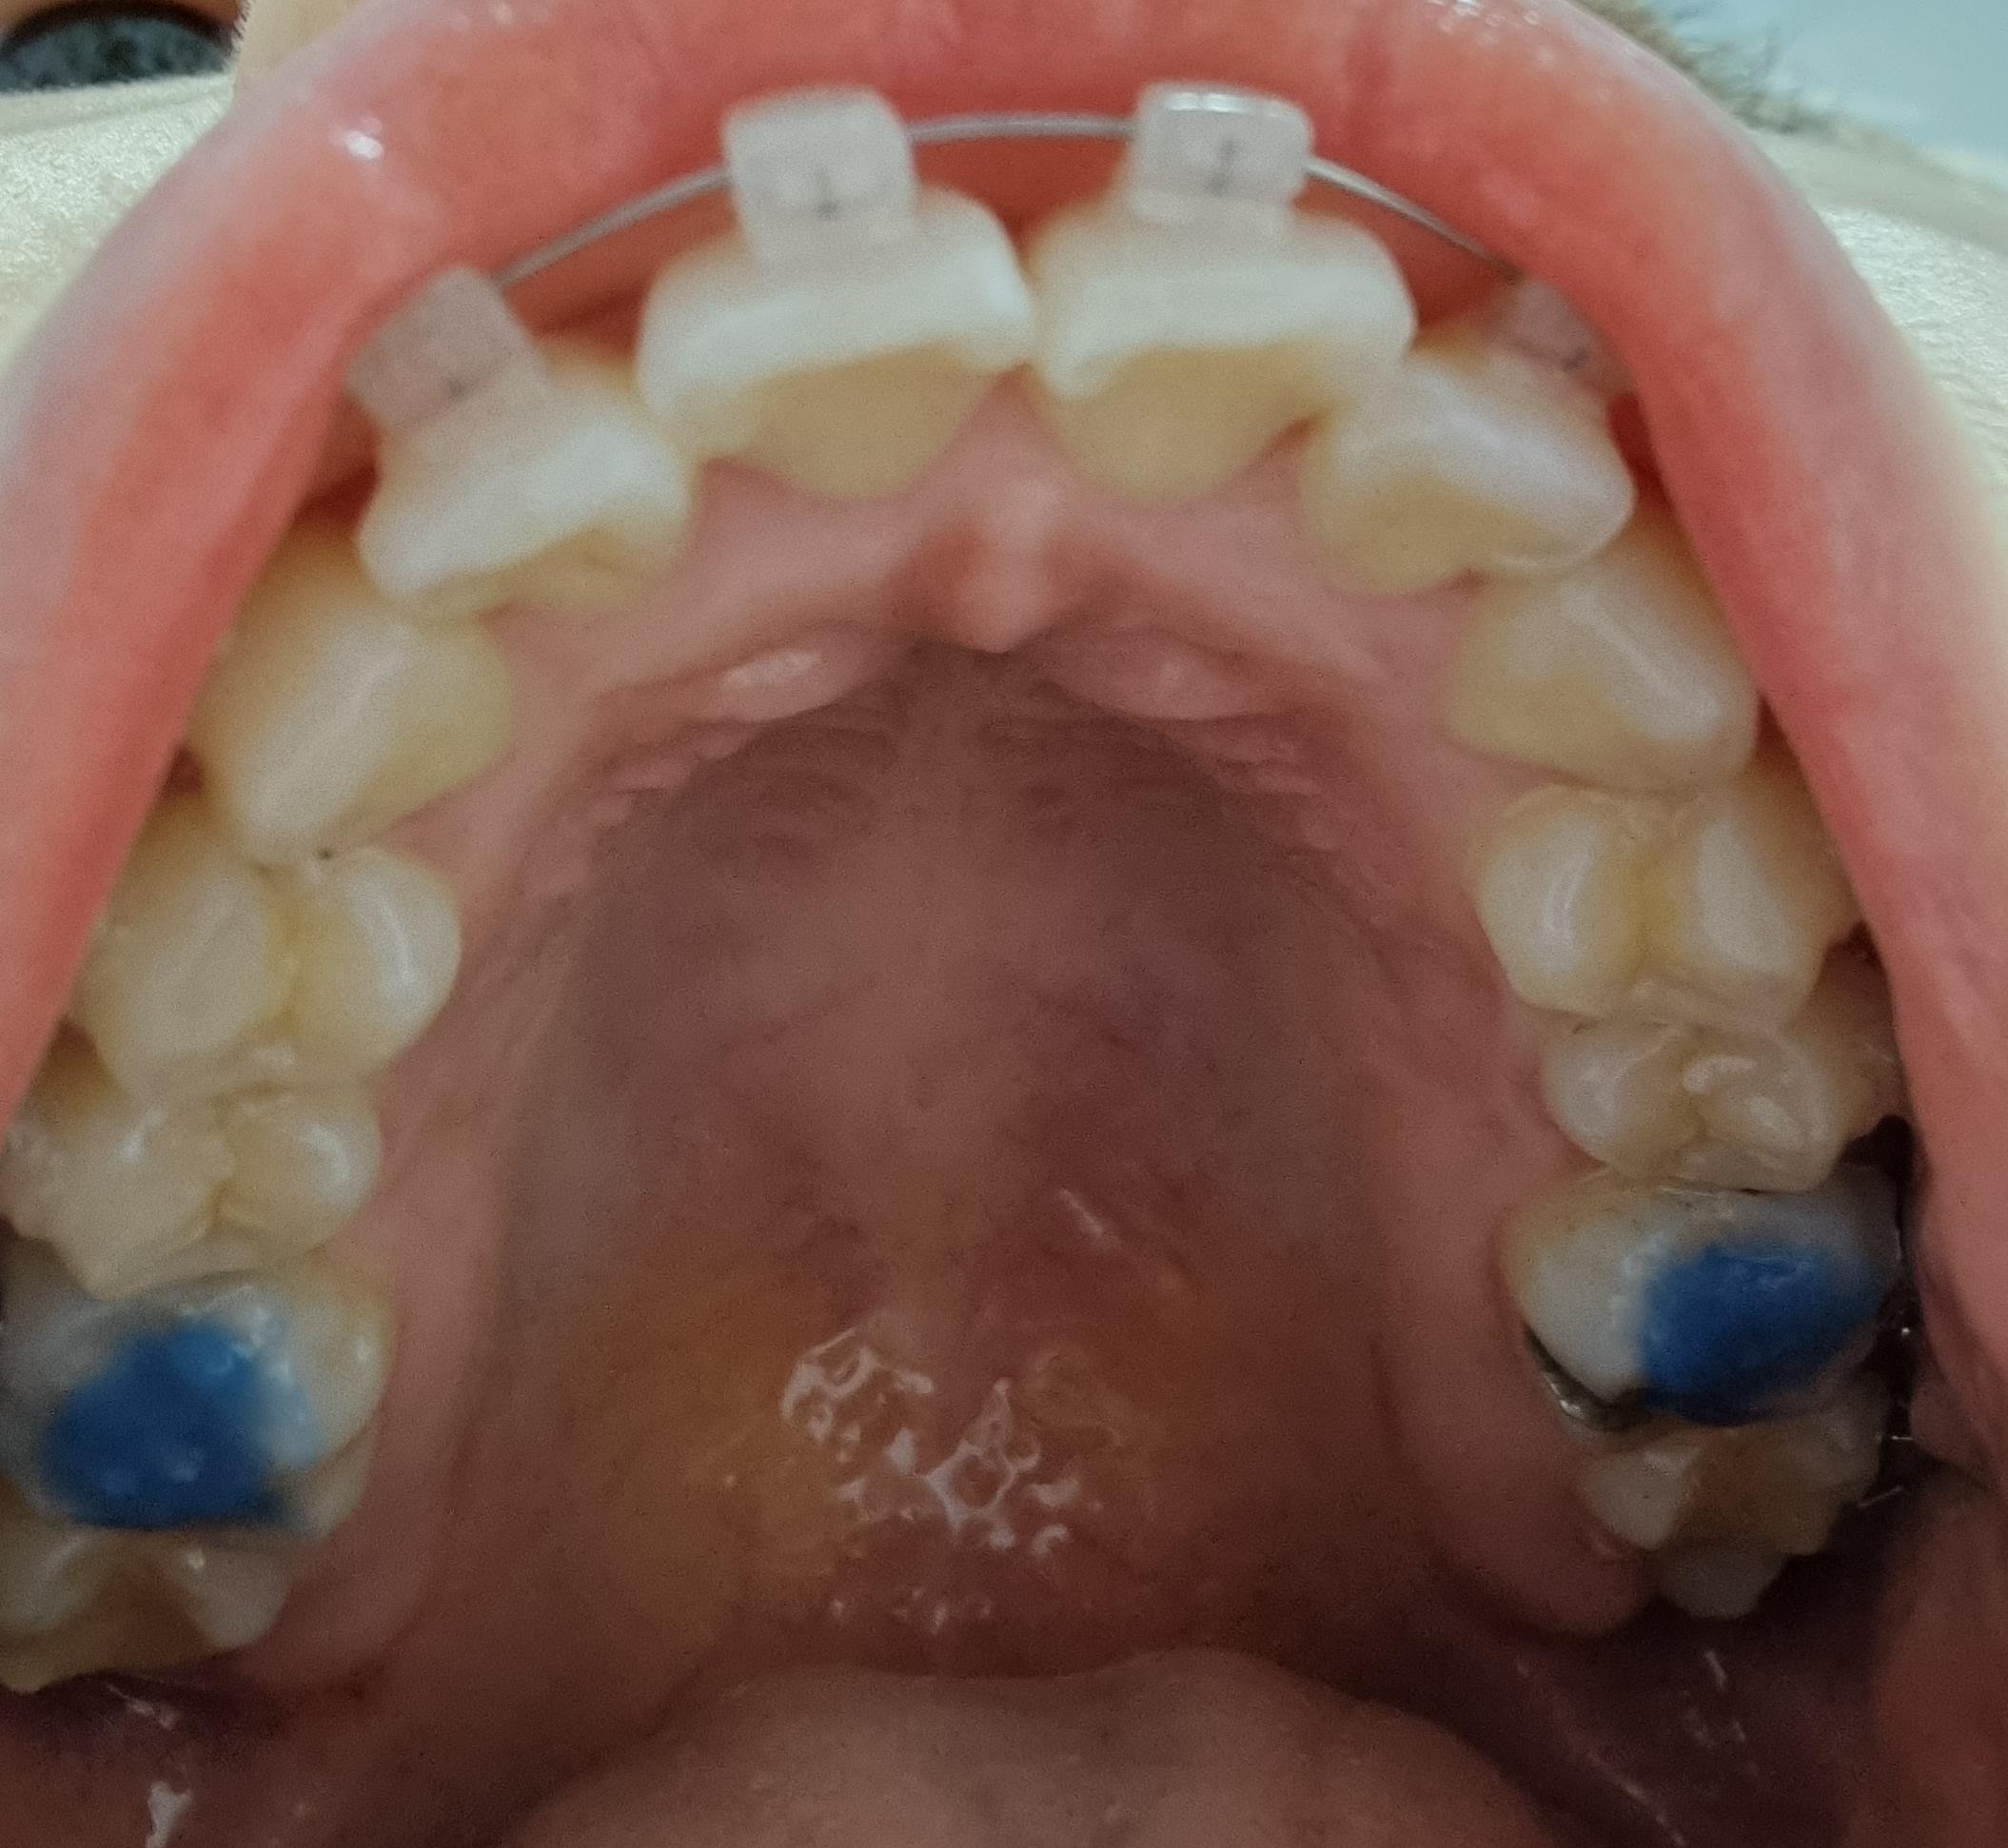

2022-03-06 2022-05-30 D+157 위의 사진은 3월달에 처음 바이트 블럭을 올렸을 때고

아래 사진은 지금 새로 올린 모습이에요.

확실히 저번보다 레진의 양이 많아졌네요.

왼쪽에 저 까만 점은 뭔지 모르겠는데

양치를 해도 손으로 긁어봐도 안없어 지네요..;;

바이트 블럭이 확실히 새로 올리니까

저작하는 느낌이 달라져서 그런지

불편한 느낌이 많이 왔습니다.